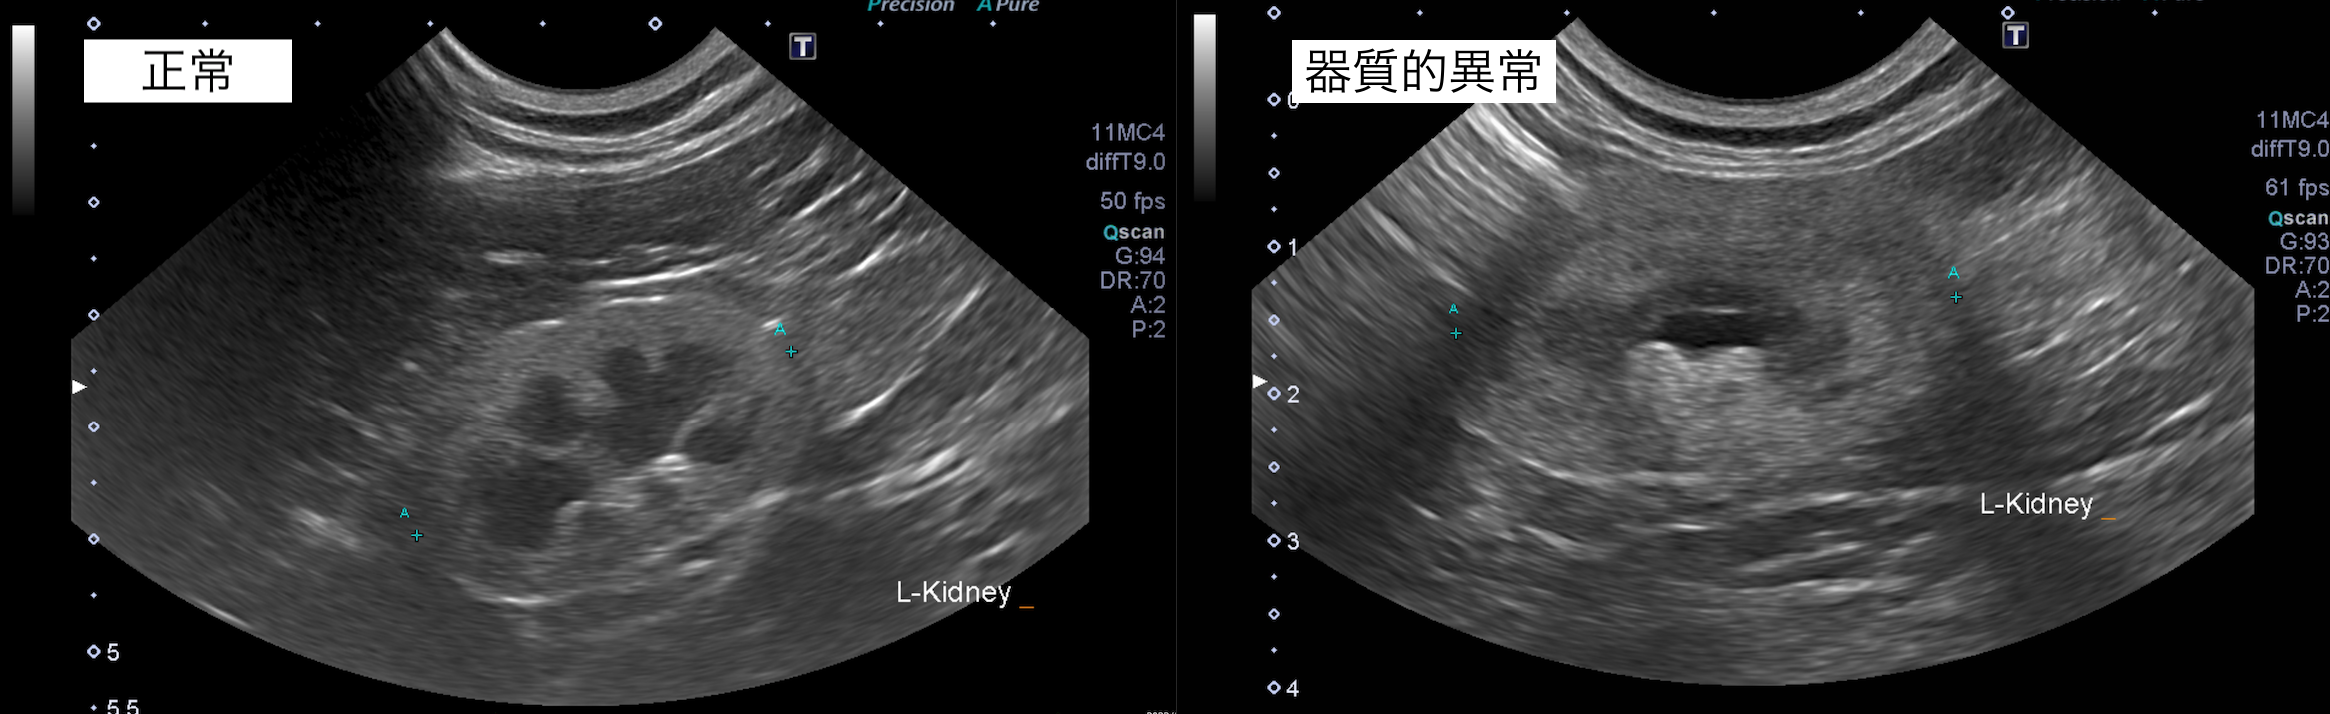

腎臓のエコー検査では器質的以上が認められ、年齢によるものだと考えております。